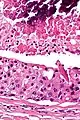

| Low magnification micrograph of a salivary duct carcinoma with characteristic comedonecrosis (left of image) adjacent to normal parotid gland (right of image). H&E stain. | |

Their histologic appearance is similar to ductal breast carcinoma.